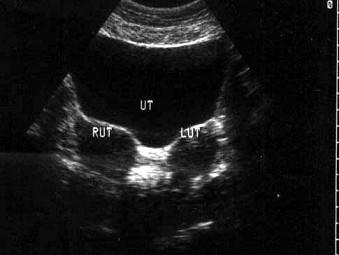

问题 女,24岁,已婚未育,体检时B超检查,如图所示,最可能的诊断为?(?)

选项 A.右附件实质性包块 B.左附件实质性包块 C.子宫肌瘤 D.双子宫 E.纵隔子宫

答案 D